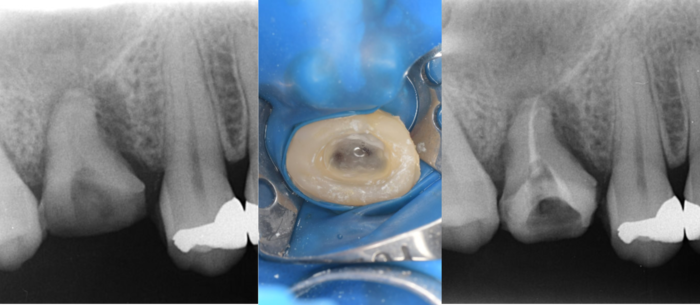

初診時デンタルX線写真

初診時デンタルX線写真とCT画像。

根管外に不透過像とそれを取り囲む透過像を認める。

コアを除去すると、分岐部へつながるパーフォレーションを認めた。

これが排膿の原因であったため、保存は困難と判断した。